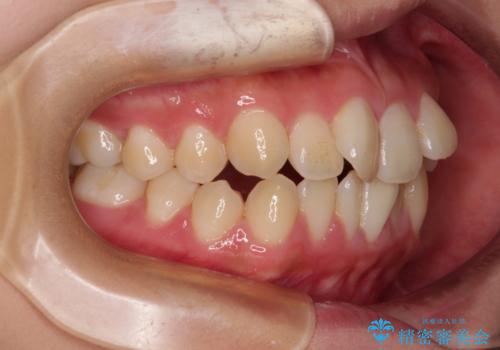

- 前歯のデコボコと唇の閉じにくさを気にして来院された患者様です。

単純に上下左右の第一小臼歯4本を抜歯して口元の突出感を改善することも考えられましたが、上顎骨よりも下顎骨の幅が広いため、より良い咬み合わせを達成することを目的として、急速拡大装置を用いて上顎骨を拡大することとしました。

歯列矯正では基本的に骨格を改善することはできませんが、急速拡大装置(MARPE)を使用することで上顎骨を側方に拡大させることができ、咬合状態を大きく改善することができます。